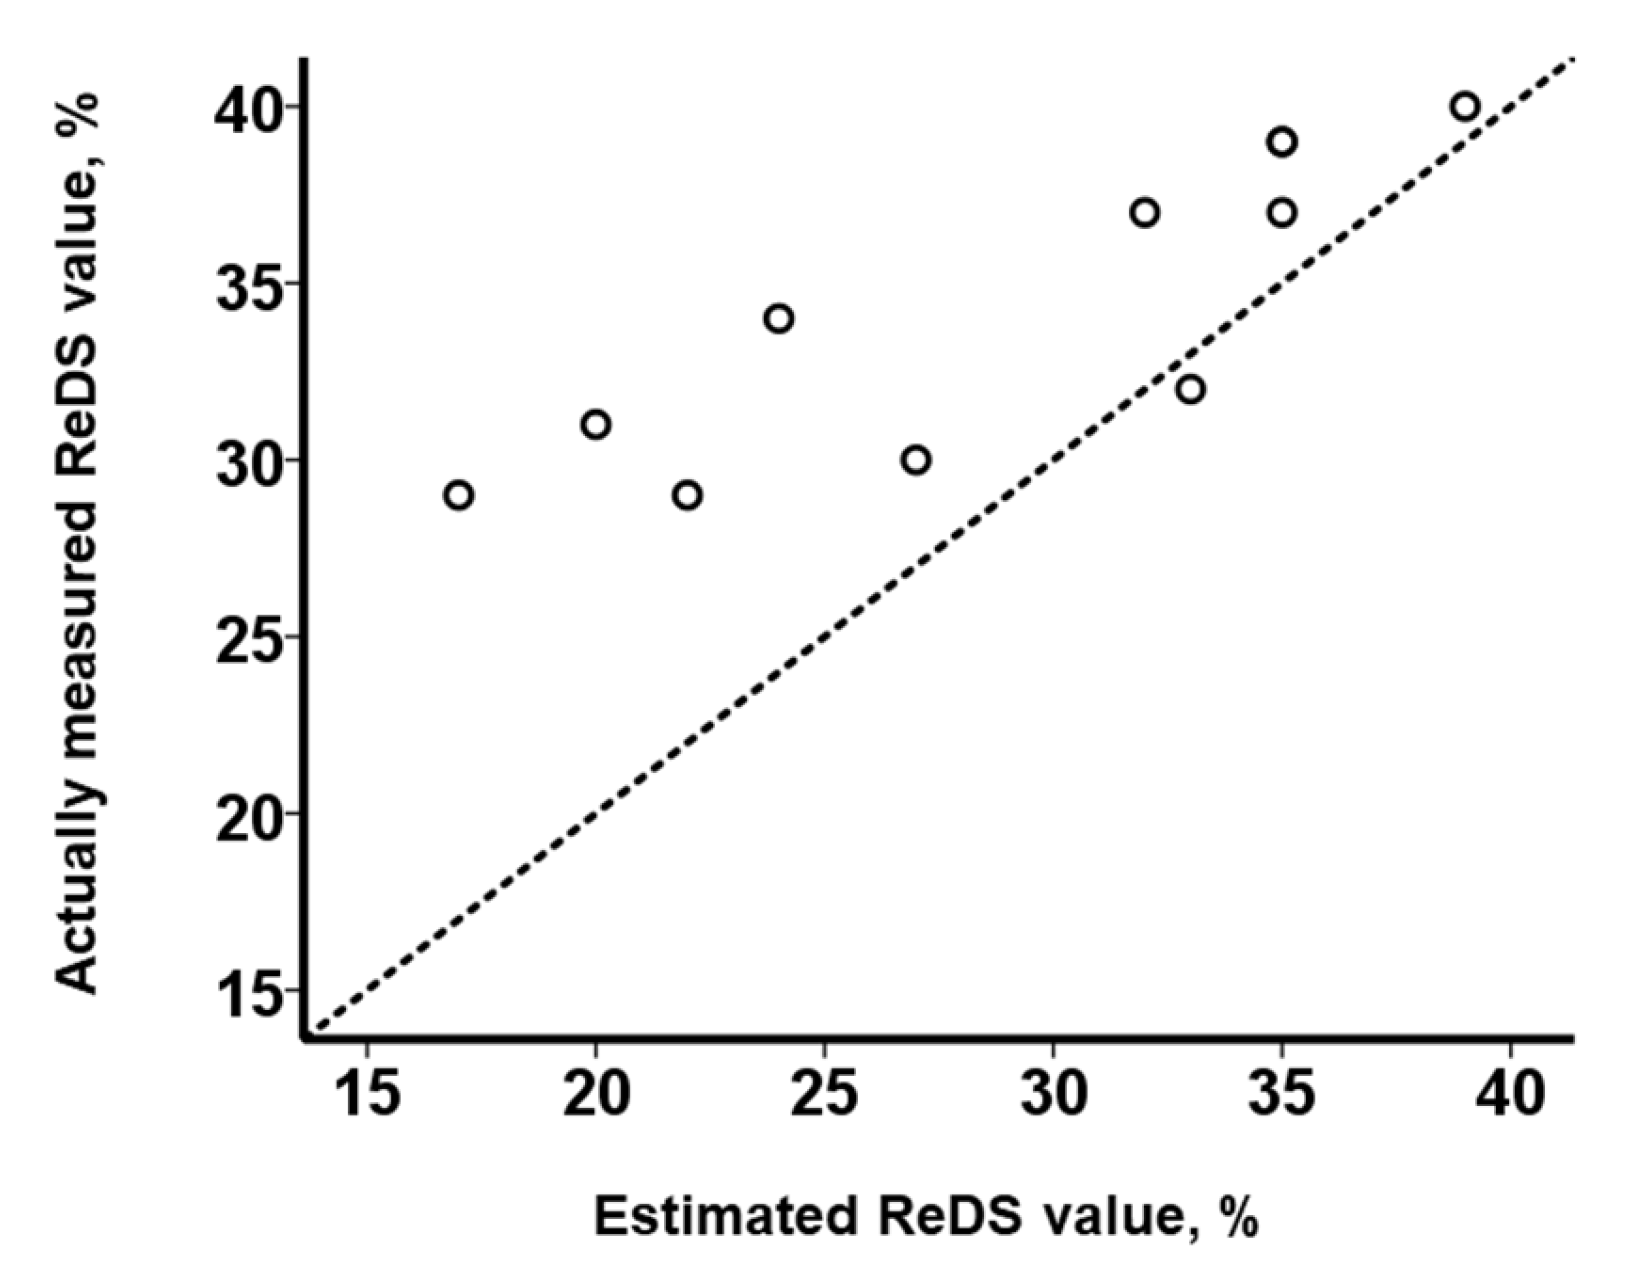

3.3. Impact of PE on the Relationship between ReDS Values and PAWP

4.1. ReDS System to Estimate PAWP Levels

4.2. Impact of the Presence of PE on the Relationship between ReDS Values and PAWP